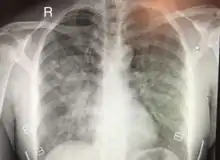

Chest x-ray of HAPE showing characteristic patchy alveolar infiltrates with right middle lobe predominance.

Hypoxic pulmonary vasoconstriction (HPV) occurs diffusely, leading to arterial vasoconstriction in all areas of the lung. This is evidenced by the appearance of "diffuse," "fluffy," and "patchy" infiltrates described on imaging studies of climbers with known HAPE.[9]

On physical exam, increased breathing rates, increased heart rates, and a low-grade fever 38.5o C (101.3o F) are common.[9][3] Listening to the lungs may reveal crackles in one or both lungs, often starting in the right middle lobe.[9][3] Imaging studies such as X-ray and CT imaging of the chest may reveal thoracic infiltrates that can be seen as opaque patches.[14][9][3] One distinct feature of HAPE is that pulse oximetry saturation levels (SpO2) are often decreased from what would be expected for the altitude. People typically do not appear as ill as SpO2 and chest X-ray films would suggest.[9][3] Giving extra oxygen rapidly improves symptoms and SpO2 values; in the setting of infiltrative changes on chest X-ray, this is nearly pathognomonic for HAPE.[3]